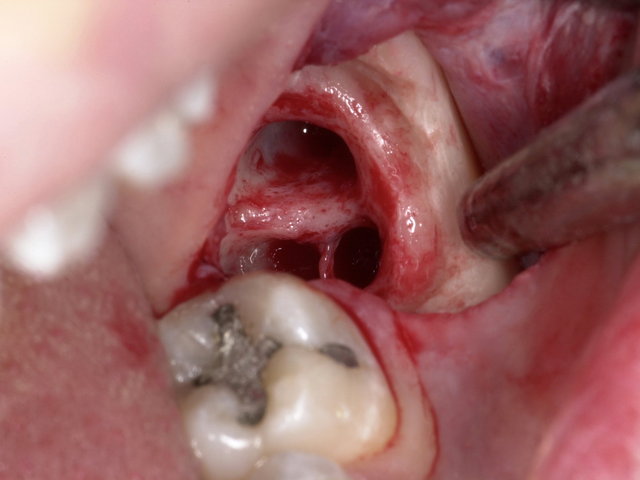

Sichtbarer Nerv im Zahnfach

Operative Weisheitszahn-Entfernung ... ✓

Operative Weisheitszahn-Entfernung ...